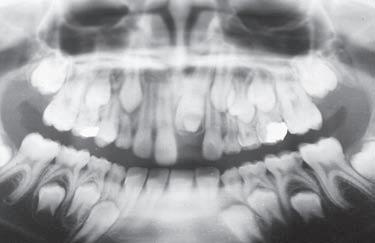

Jsem stále více přesvědčena o tom, že informaci o přítomnosti ortodontické anomálie, která se plně projeví až za několik let, máme k dispozici velmi brzy. Určitá podezření můžeme vyslovit obvykle už při zahájení první fáze výměny chrupu. Jen je třeba dobře se dívat a věnovat pozornost nenápadným symptomům, které na ni upozorňují. Jinak se budeme neustále setkávat s udivenými dospělými pacienty s retinovanými špičáky, s perzistujícími dočasnými zuby a s pacienty, jejichž chrup nelze kvůli ortodontické anomálii dobře ošetřovat.